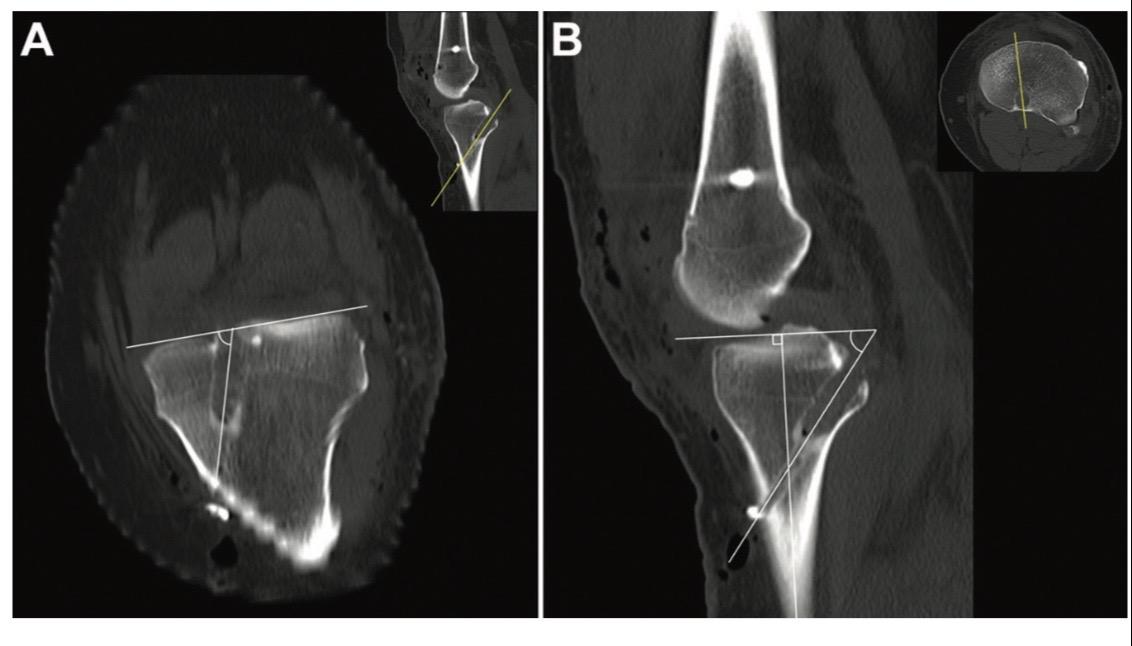

后交叉韧带重建。后交叉韧带(PCL)重建手术中,适当的隧道位置、隧道角度和移植物角度对于维持PCL移植物的稳定性和机械性能至关重要!